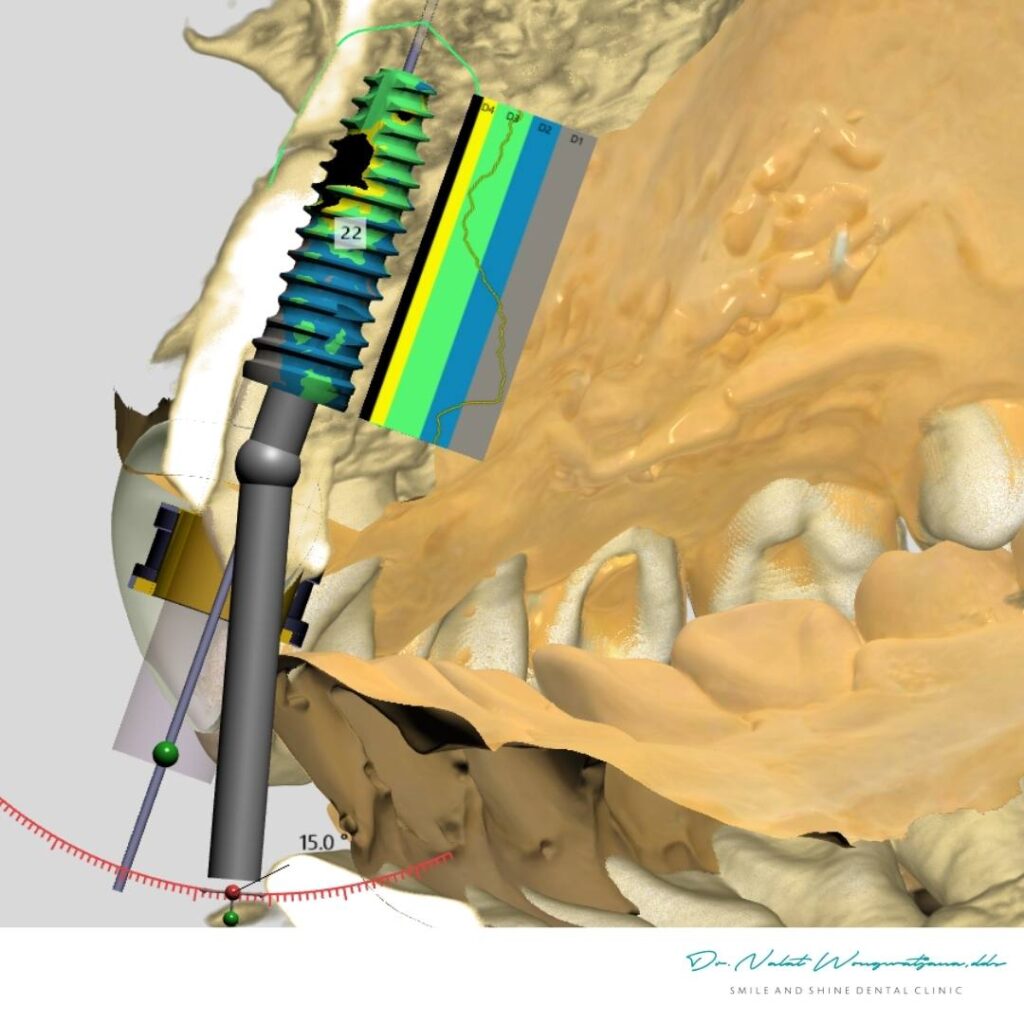

หนึ่งในข้อดีของ Computer Guided Implant (Static Guide)

คือการวางแผนตำแหน่งรากฟันเทียมแบบดิจิทัลล่วงหน้า

- ออกแบบตำแหน่งรากฟัน

✔ ด้านความแม่นยำ

Digital planning ทำให้ตำแหน่งรากสัมพันธ์กับฟันในอนาคตตั้งแต่ต้น

- ปริมาณกระดูก

- ความแข็งแรงของกระดูก